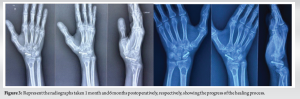

A 58-year-old right-hand-dominant male presented with pain and stiffness in his right wrist, which has been ongoing for several months. The initial injury occurred 8 months ago when he fell onto his outstretched hand. The patient is a non-smoker and has generally been in good health. He was previously diagnosed with a scaphoid fracture and opted for conservative management at the time. However, over the past few months, he has experienced worsening pain and stiffness, which have been affecting his ability to perform daily activities. There is no history of any further trauma since the initial injury. Radiographs revealed a fracture through the waist of the scaphoid, accompanied by a notable humpback deformity. A CT scan was performed to assist in further planning and to confirm the union status of the fracture. In addition, an MRI was conducted to assess for any signs of avascular necrosis in the proximal fragment, which appeared to be within normal limits (Fig. 1). We reviewed the management options with the patient, including the possibility of salvage surgery if the primary intervention failed. A right scaphoid open reduction and internal fixation were performed using Herbert screws, along with a cancellous bone graft harvested from the radius through the same incision. A bone substitute, tricalcium phosphate, was also used. Postoperatively, the patient was placed in a below-elbow slab for a period of 4 weeks (Fig. 2a-d). The patient was started on a range of motion exercises of the wrist and thumb including Handgrip exercises and tabletop exercises. Heavy weight lifting was prohibited for the whole follow-up period. The patient was followed up for a period of 6 months, during which his range of motion showed significant improvement. The DASH (Disabilities of the Arm, Shoulder, and Hand) score decreased from 46 at the time of admission to 8 at the 6-month post-operative follow-up. The patient reported no functional disability at this stage. Six months following the procedure, the patient exhibited good wrist function and grip strength. The range of motion of the wrist increased from 40° of flexion and extension preoperatively to 80° flexion and 70° extension post-rehab. Radiographs showed clear signs of fracture union (Fig. 3).